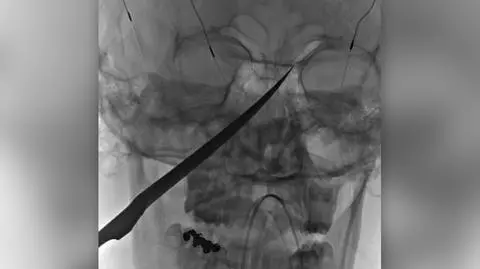

15-letni Eli Gregg z Redfield w amerykańskim stanie Kansas może mówić o wielkim szczęściu. Chłopak przeżył po tym, jak 25-centymetrowy nóż przebił jego twarz i utknął w czaszce. - To niemal cud, że udało się bezpiecznie wyciągnąć ostrze - mówi Jimmy Russell, matka nastolatka.

Nóż zatrzymał się w czaszce chłopaka tuż przed mózgiem. Ostrze dotykało tętnicy szyjnej, która zaopatruje mózg w krew.

- Gdyby nóż wywierał większy nacisk, nie sądzę, by to przeżył - mówi dr Koji Ebersole z University of Kansas Health System, który nadzorował wydobycie ostrza z głowy chłopaka.